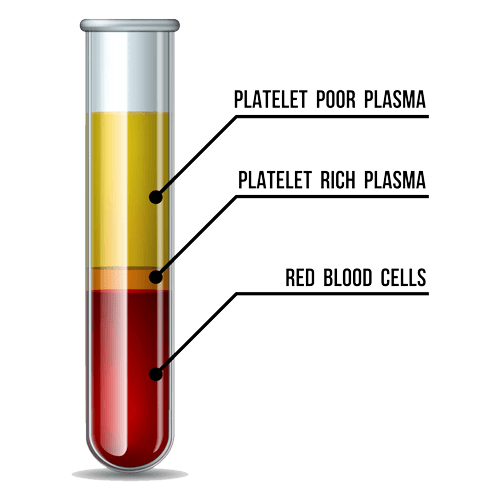

PRP (Platelet-Rich Plasma) Autologous regenerative treatment injecting platelet-rich plasma from your own blood. Growth factors from platelets promote tissue regeneration and collagen synthesis without rejection.